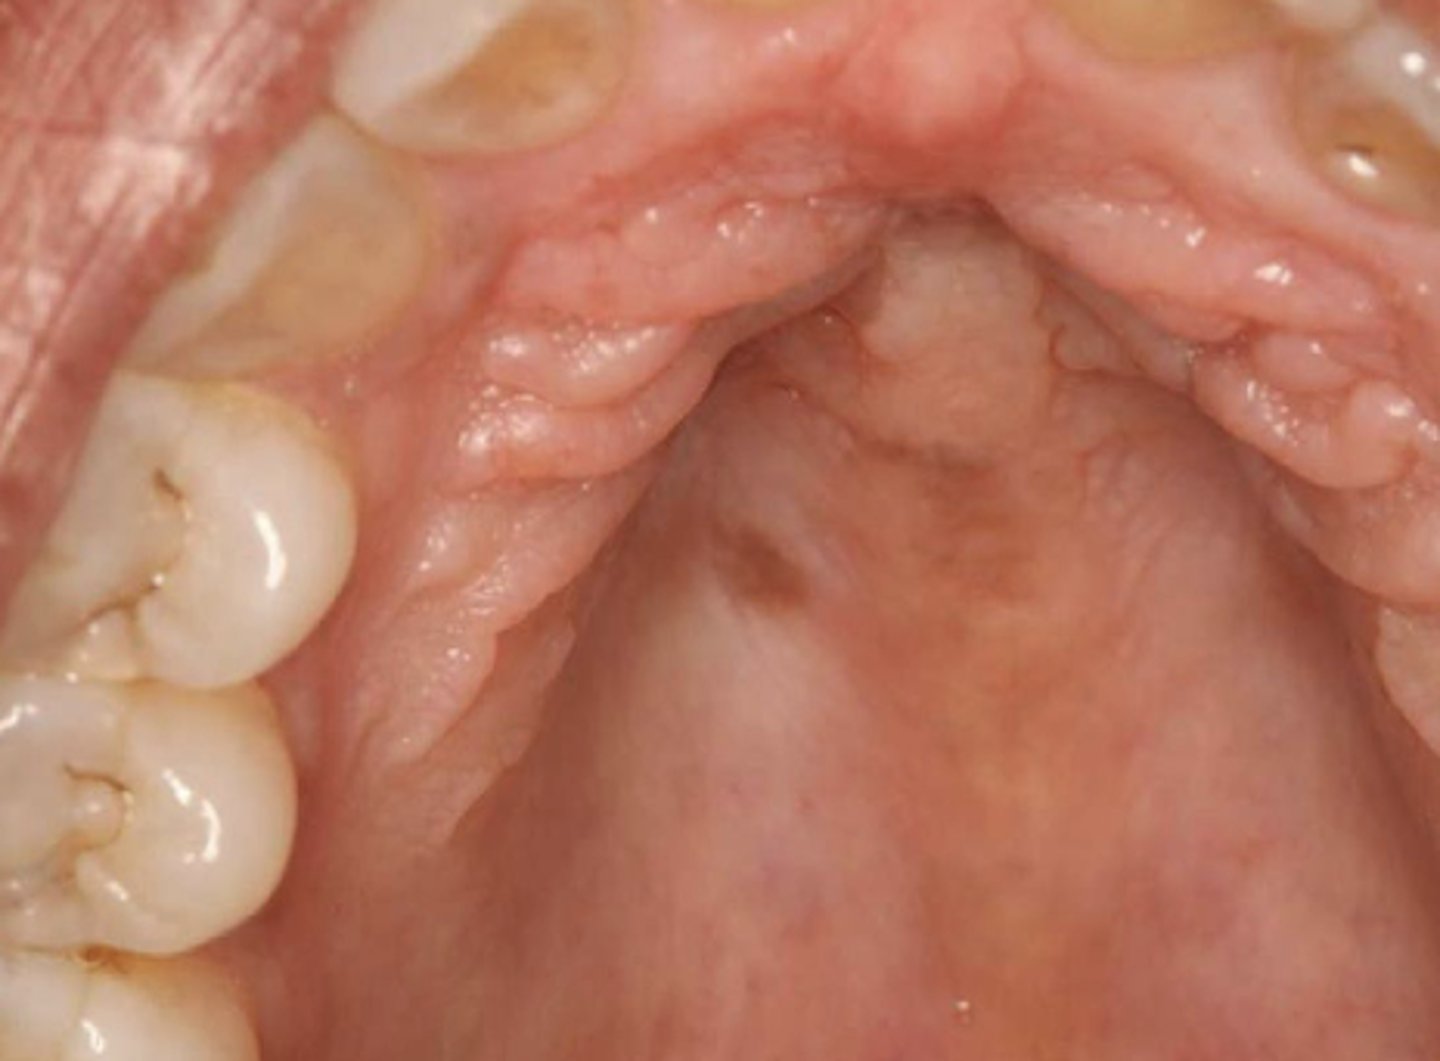

What type of pigmented lesion?

- Rare acquired pigmented lesion(s) of rapid onset

- Reactive?

- May reach several cm in size

oral melanoacanthosis (a.k.a. oral melanoacanthoma)

Oral Melanoacanthosis has a predilection for which ethnic group and which gender?

African American females

Oral Melanoacanthosis usually appears at which age?

3rd-4th decades

What is the differential diagnosis?

45 year-old African American female presented with this asymptomatic lesion for 2 months.

oral melanoacanthosis

What pigmented lesion has these histopathologic features?

- Dendritic melanocytes throughout epithelium

- Thickened epithelium

- Increase in basal layer melanocytes

- Spongiosis and mild acanthosis

What is the treatment of oral melanoacanthosis?

- Biopsy to r/o melanoma

- No further rx required